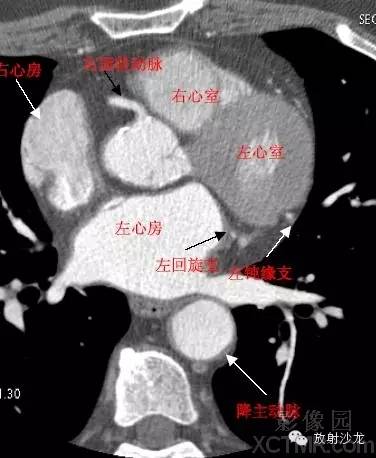

心脏冠状动脉CT解剖中文详细标注

LA -Left Atrium左心房

RA -Right Atrium右心房

LV -Left Ventricle左心室

RV -Right Ventricle右心室

D. Aorta-Descending Aorta降主动脉

LCX -Left Circumflex Artery左回旋支

LMB -Left Obtuse Marginal Branch 左边缘支(钝缘支)

GCV–Great Cardiac Vein心大静脉